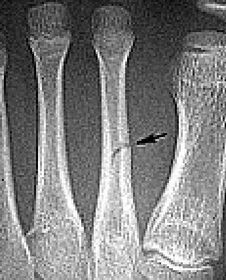

What disease is this? What does the arrow indicate? | Rheumatoid arthritis. Arrow = Bone erosion secondary to inflammation of retrocalcaneal bursa. |

What disease is this? What do the arrows indicate? | Gout Arrows = 'punched out' erosions |

What disease is this? What indicates this? | Tophaceous gout. Soft tissue swelling surrounding the index finger PIPJ, with associated erosion and bone resorption |